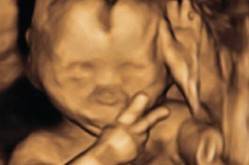

بريطانية ذهبت لتصوير جنينها فوجدته "يلوح" بعلامة النصر!